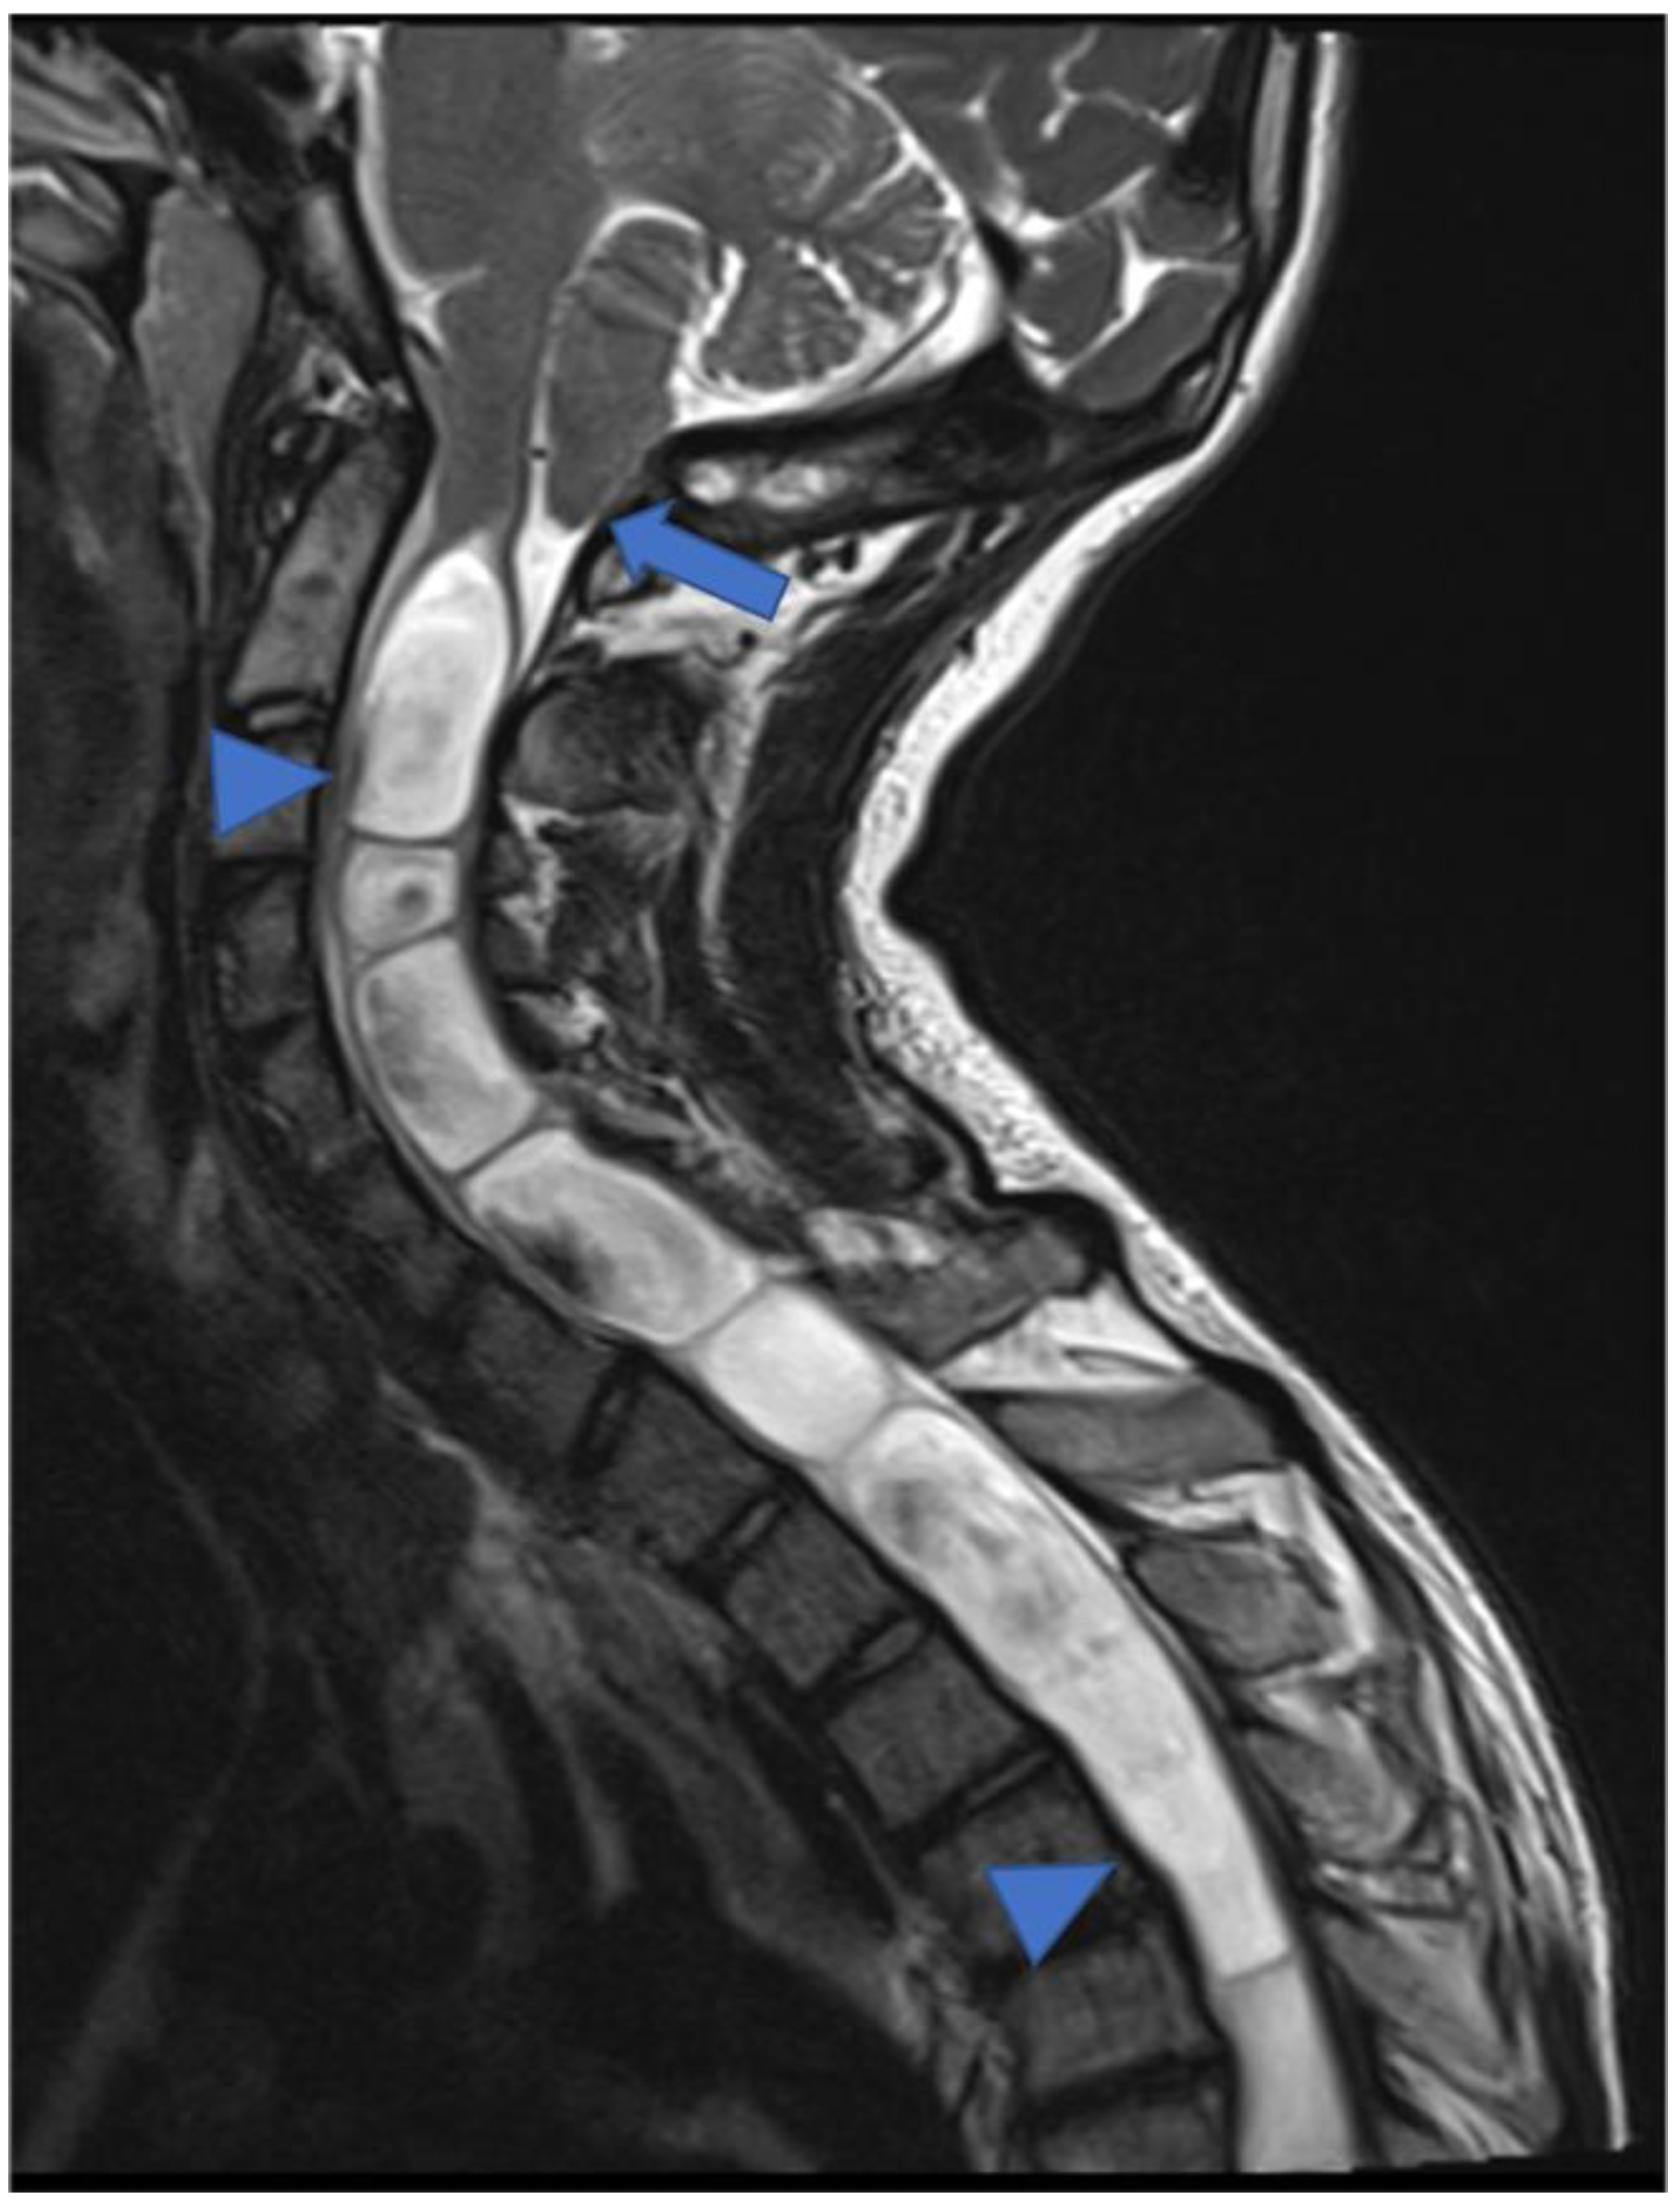

Figure 10.

Gadolinium-enhanced T1-weighted image. Craniocervical junction meningioma (arrow) characterized by dural base, well-defined margins, and intense and homogeneous enhancement. Compression and anterior dislocation of the bulb and cervical cord are evident (arrowhead).